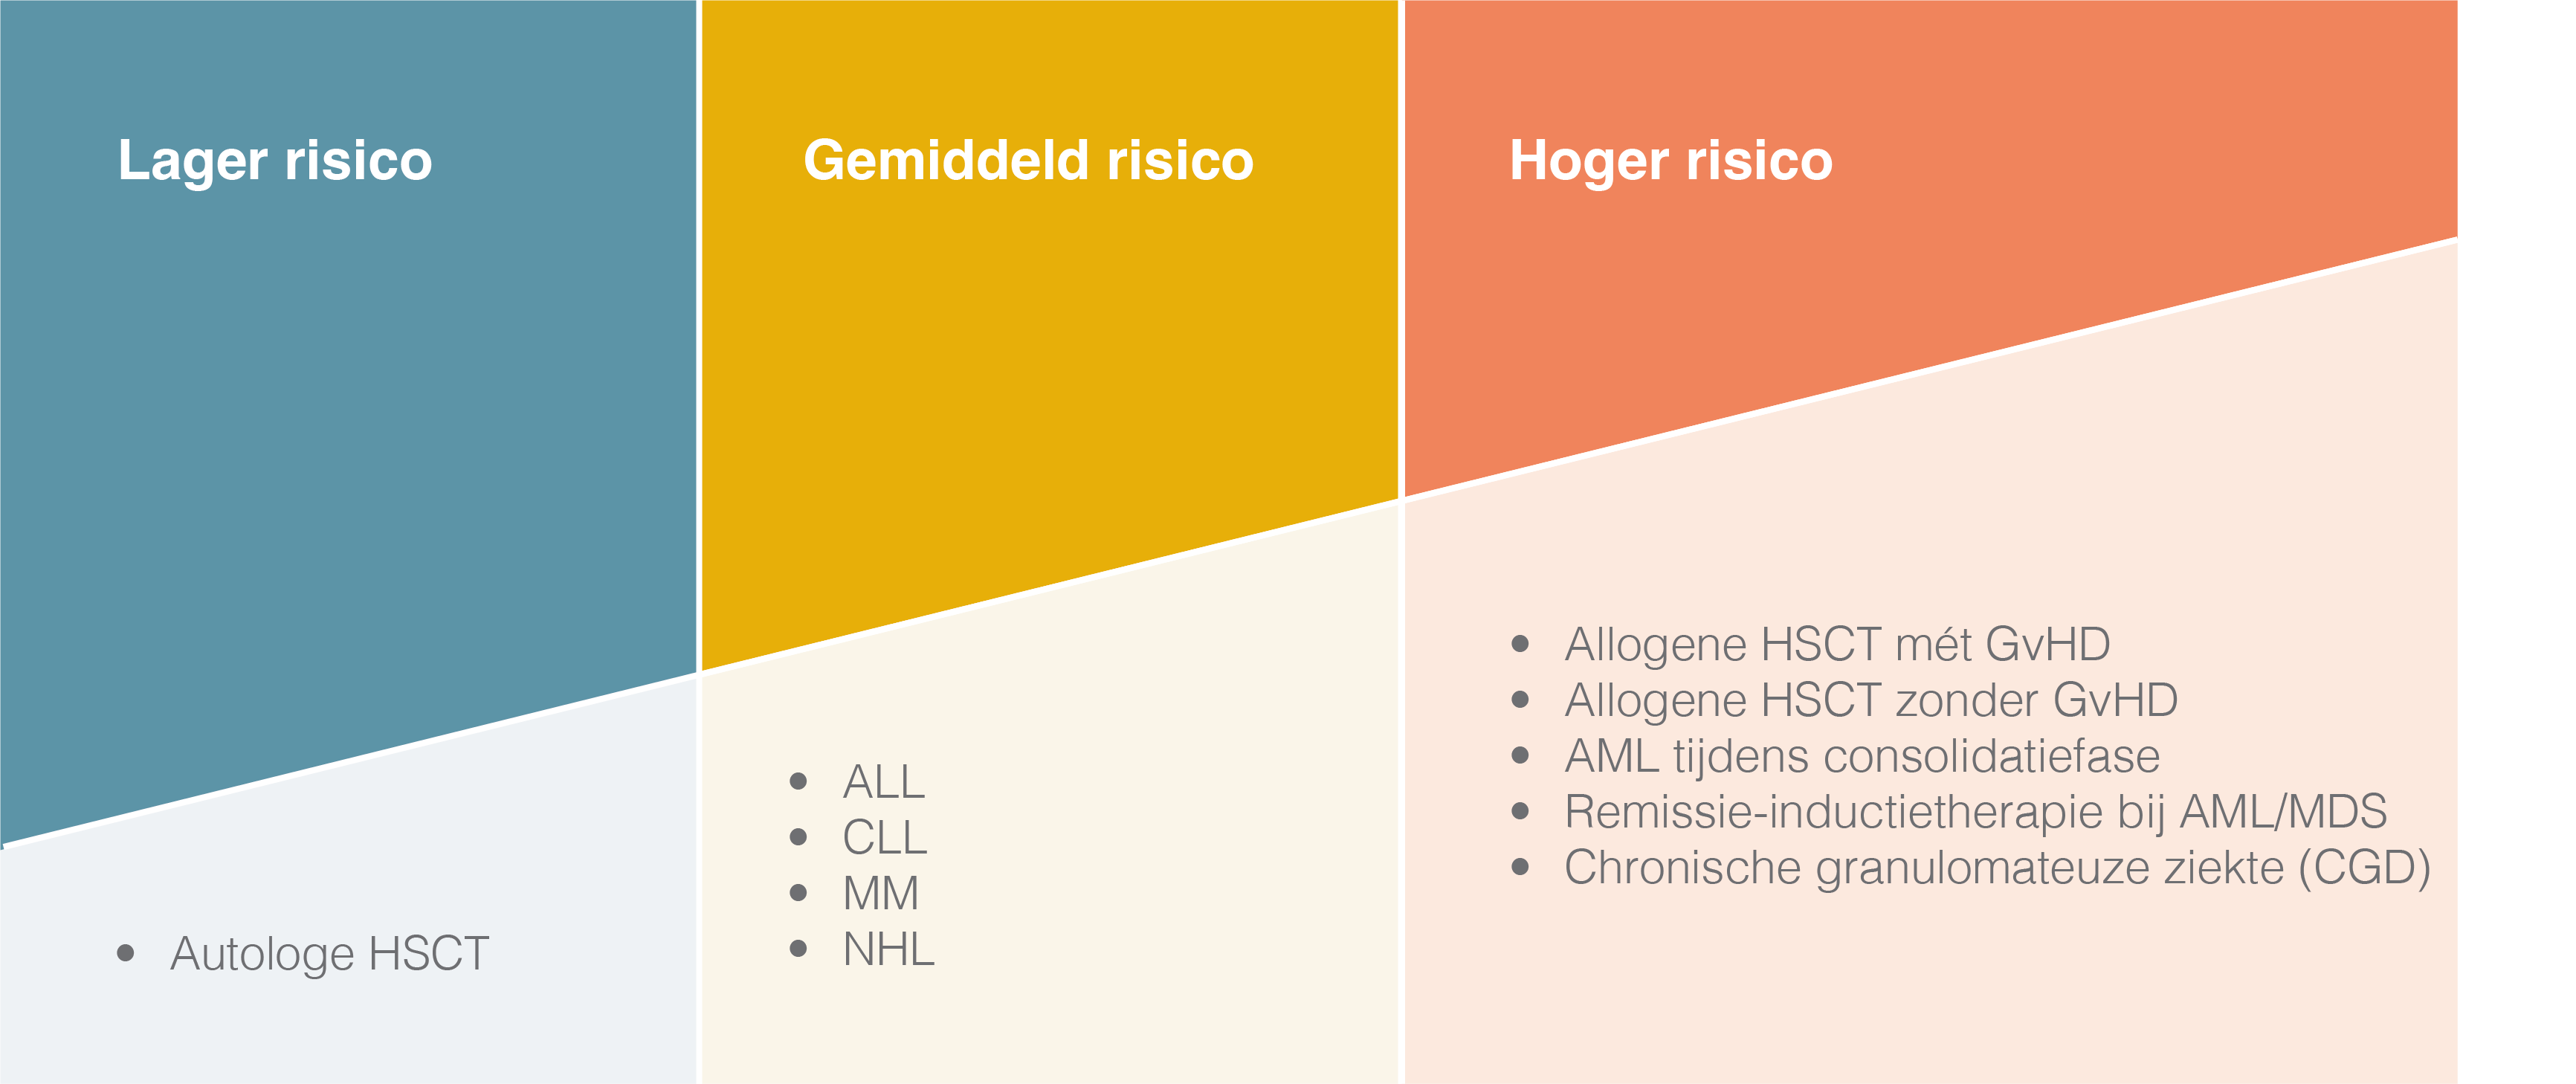

Figuur 2. Het risico op invasieve aspergillose door hematologisch ziektebeeld of behandeling. Overgenomen en bewerkt van Herbrecht R et al. 201272